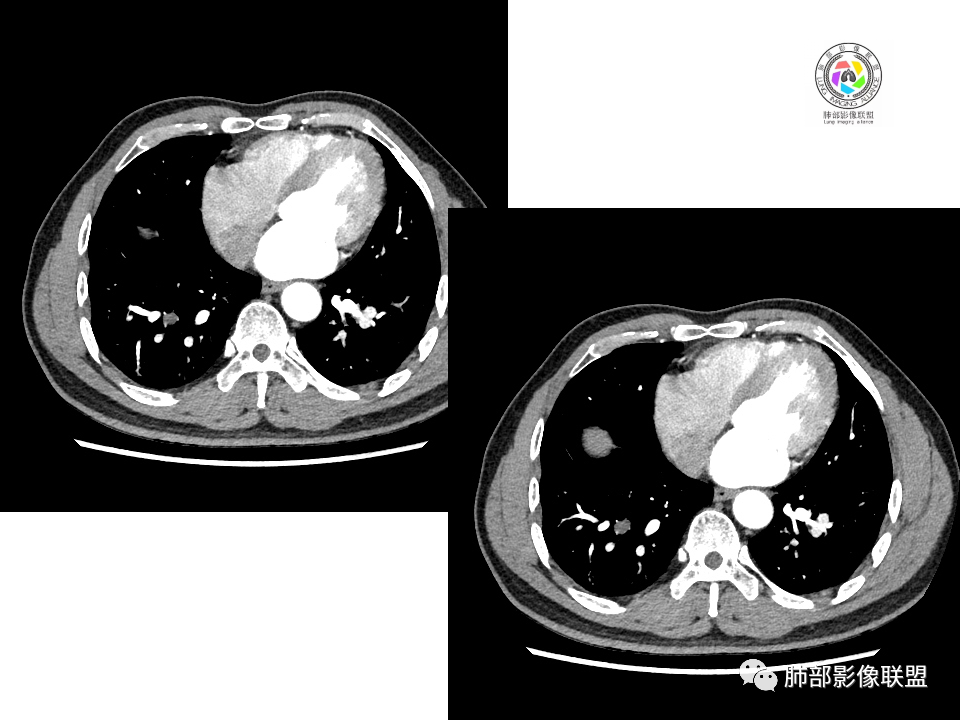

右肺下叶背段胸膜下见团块影,边缘清,其后基底段见一扁平状结节,各见‘’平直及桃尖"征,均轻度强化,右肺上叶背段及中叶外侧段分别少许纤维化灶及部分卫星病灶,一元考虑TB,与隐球菌鉴别!

右肺下叶胸膜下类圆形团块,边缘光滑无毛刺分叶,强化均匀无坏死,另血管旁小结节平直桃尖,上叶小斑片影,考虑结核或者真菌感染。

右肺下叶背段胸膜下见一边缘稍模糊、浅分叶结节灶,密度均匀,似乎轻度均匀强化(具体CT值看不出来),与胸膜锐角相贴,似有平直征和桃尖征。此病灶前内侧还有类似小结节,轻度强化,右肺上叶后段有斑片状稍高密度影:考虑良性病变,炎性结节可能。

晨读,右肺下叶背段胸膜下见肿块影,边缘清晰,未见与气管相连通,右下叶见结节影边缘清晰,两处病变密度均匀,同步不明显强化,中叶外侧段斑点状影,树芽征,考虑1良性病变,结核?隐球菌?2淋巴瘤待除外。

右肺下叶背段胸膜下宽基底团块状占位,浅分叶,边界清晰,胸膜下脂肪间隙清晰,背段支气管管壁似乎增厚,未见明显强化。外侧基底段血管束间结节,边界清晰,亦未见明显强化。中叶外侧段见少许树芽征象。纵隔未见明显肿大淋巴结。我先猜个结核。

男性,49岁,体检发现,右肺下叶背段胸膜下见肿块,边界清楚,边缘光滑,胸膜下脂肪间隙存在,有分叶,无毛刺,均匀强化,内无坏死,右肺下叶血管束间不规则实性结节,边界清楚,无明显强化,中叶少许斑片状高密度影,纵隔未见明显增大淋巴结,考虑良性病变。

右下肺占位并淋巴结肿大,边缘光滑,强化不明显,指状突起。考虑恶性肿瘤,不除外小细胞,鉴别诊断肺结核。

中年男性,体检发现病灶,右肺下叶背段胸膜下见团块影,边缘清晰,与气管关系不密切,右肺下叶见一小结节影,边缘清晰,两处病变密度均匀,增强病灶强化不明显,偏向良性病变,隐球菌?炎性假瘤?

右肺下叶肿块,边界清楚,边缘有晕,光滑,无毛刺,均匀强化,无坏死,中叶少许斑片状高密度影,粘液栓,考虑良性病变,隐球,鉴别结核。

中年男性,有吸烟史,右肺下叶靠近胸膜下类圆形肿块,边缘光滑,有膨隆,浅分叶,周围有磨玻璃影,附近有血管进入,与支气管关系不大,宽基底与胸膜相连,胸膜增厚不明显,密度均匀,轻度强化;右肺下叶近端有一不规则结节,有血管贴边征,右肺中叶外侧段斑片影。右肺下叶靠近胸膜下肿块考虑恶性神经内分泌肿瘤,大细胞肺癌可能性大。靠近肺门端结节考虑转移?右肺中叶炎症。鉴别隐球菌肺炎。

中年男性,无症状,右肺下叶背段团块影,边缘清晰,周围晕征,增强病灶强化不明显,考虑隐球菌。

右肺下叶二个大小结节,胸膜下结节浅分叶,指状突起,轻度强化,较小结节血管漂浮,考虑小细胞癌,类癌,鉴别隐球菌。

右肺多发结节,较大位于胸膜下,宽基底与胸膜相连,边缘光滑,分叶不明显,局部周围似有模糊GGO,支气管显示不佳,平扫密度均匀,增强后强化不明显,考虑良性,IMT,隐球菌,鉴别小细胞癌。

右肺下叶胸膜下肿块影,边界清晰,无明显分叶及毛刺,无晕征,未见明显卫星病灶,内无钙化,增强后均匀强化,未见明显坏死,近肺门侧小肿块,与血管无关,需要连续层面看与支气管的关系,无关就是淋巴道,考虑小细胞癌有可能,近肺门是淋巴转移途径?

体检发现右肺下叶胸膜下类圆形肿块,边界清晰,有膨胀感,胸膜下脂肪间隙清晰,密度均匀,增强轻度均匀强化。另右肺下叶血管束间可见一小结节影,与胸膜下大结节类似。考虑为良性病变。

中年男性,体检发现,有吸烟史。影像见右肺多个结节、肿块影,大者位于背段,靠近胸膜下类圆形肿块,密度较均匀,边缘光滑,有膨隆,浅分叶,周围有磨玻璃影,有血管进入,似与支气管关系不大,宽基底与胸膜相连、扶墙,轻度强化;纵隔内无明显肿大淋巴结。首先考虑炎性隐球菌可能,需鉴别:肿瘤病变转移。

哦落花时节

毛勤香

中年男性,体检发现占位。右肺下叶背段胸膜下肿块,周围晕征,有小分叶,与支气管、肺内血管关系不清,形似山丘,重建可见肿块呈D字形凸向肺部。似跨斜裂,似有小凸起与肋下缘相连,增强似有轻微均匀强化。右肺下叶外基底段小结节,位于血管周围,部分边缘平直,轻微均匀强化。考虑二元:一、右下叶背段肿块为肺外病变,神经鞘瘤?SFT?鉴别小细胞癌、隐球菌病;二、右下叶外基底段结节考虑为良性结节、炎性肉芽肿?

大小两个结节,形态类似,强化一致,都是乏血供病变,也无明显坏死,不符合炎性肉芽肿强化特点了,大结节膨隆明显,有局部突出,有长期吸烟史,所以考虑神经内分泌肿瘤可能(小细胞>不典型类癌),另外不典型错构瘤需要鉴别。最终还是需要穿刺病理确定。

血管也是稍推移,在边缘,病灶密度均匀,边缘稍收缩;均匀强化;

这两个病灶的密度、强化、形态、边缘、与血管的关系类似;还是一元论吧。

2.右肺下叶背段胸膜下块影,边界清楚光整,上下极见磨玻璃晕,未见明显分叶毛刺和棘状突起,未见胸膜凹陷或胸壁侵入。密度均匀,轻度不均匀强化。未见支气管进入。

3.右肺中叶外侧段胸膜下散在小片影,磨玻璃密度为主,边界不清,支气管相关。符合炎性特征!

4.右肺下叶基底段支气管血管束旁小结节影,边界清楚,强化不明显。注意,这结节在“遥远的”基底段。